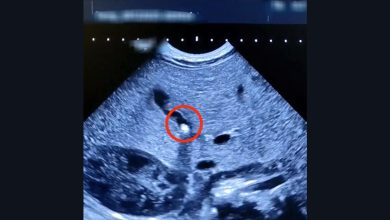

40 таблеток за один раз: подросток на ИВЛ после ссоры с подругой

Трагедия, которая едва не оборвала жизнь 16-летней девушки, произошла на почве обычной подростковой ссоры. Пациентка с тяжелым психиатрическим диагнозом оказалась…